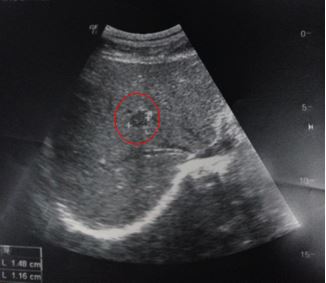

-          Siêu âm ổ bụng:

Hình 2:Siêu âm ổ bụng:nhu mô gan phải có nốt giảm âm kích thước 15 x 12 mm (vòng tròn đỏ), nghĩ tới tổn thương thứ phát